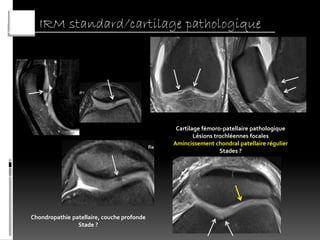

IRM standard/cartilage pathologique

Cartilage fémoro-patellaire pathologique

Lésions trochléennes focales

Amincissement chondral patellaire régulier

Stades ?

Chondropathie patellaire, couche profonde

Stade ?